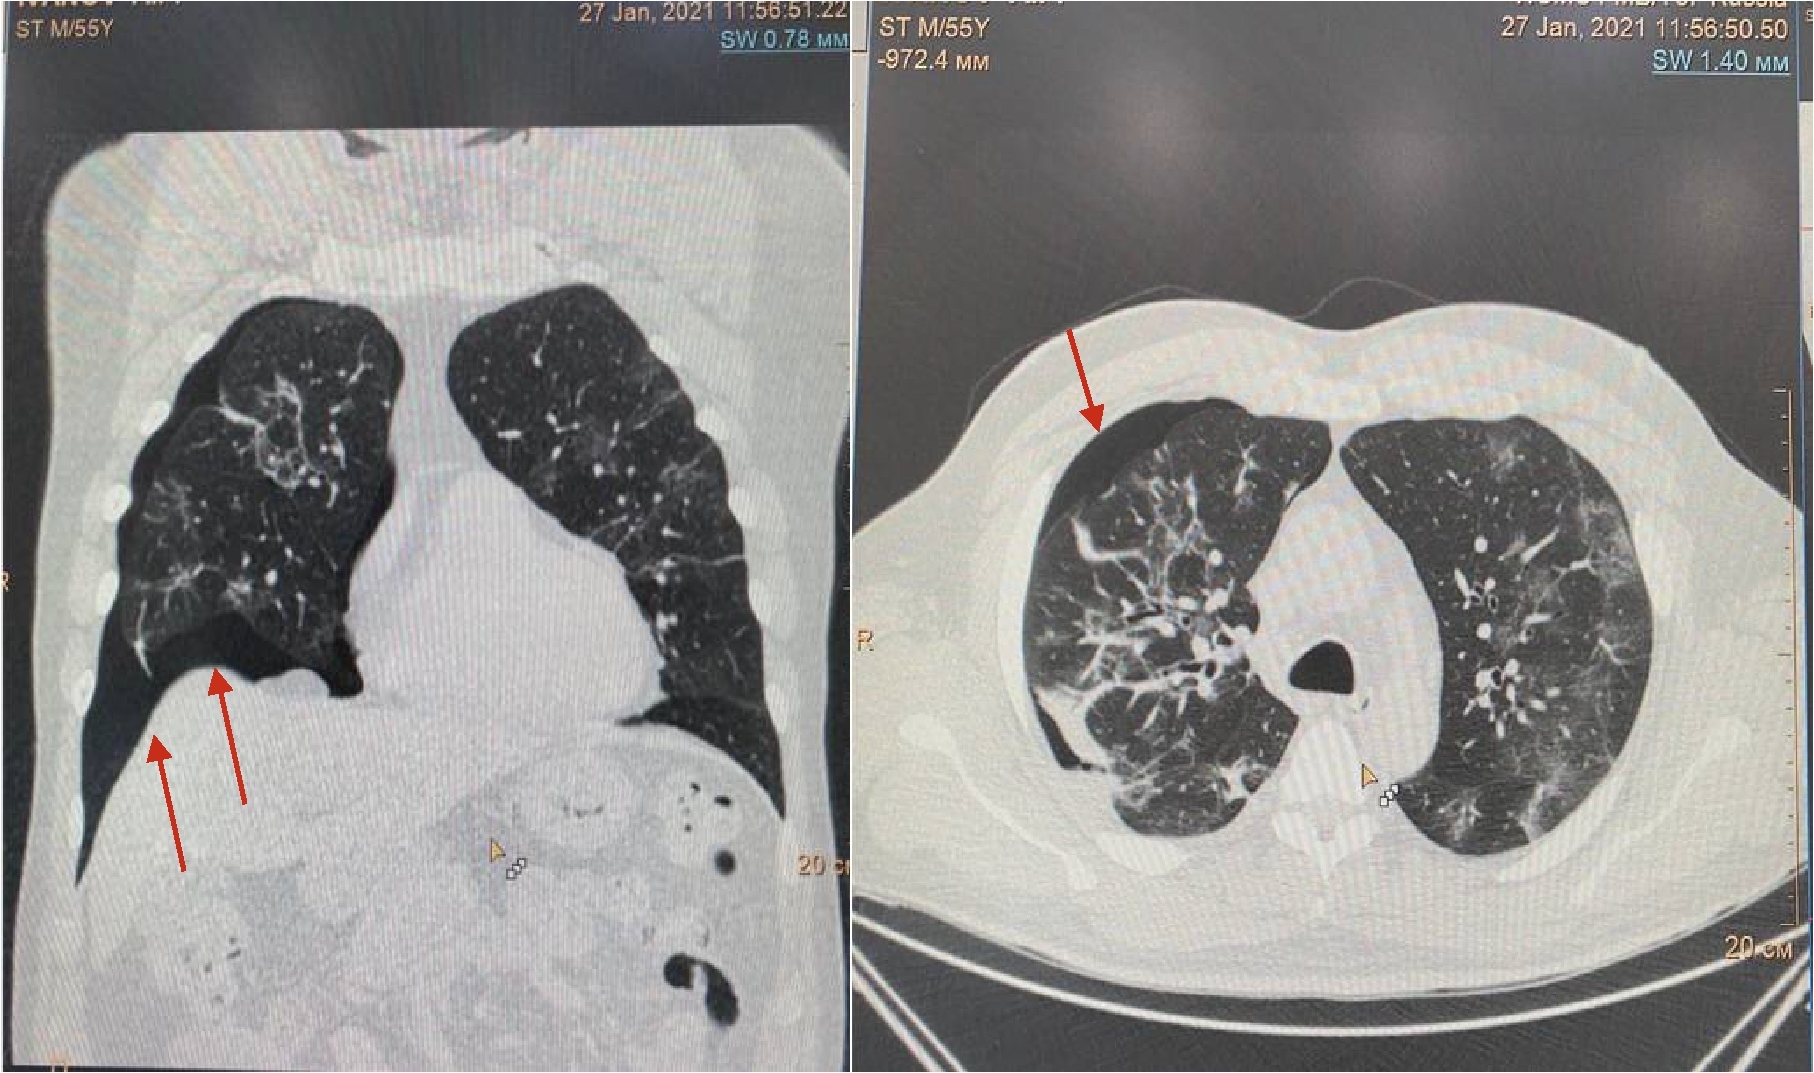

Рисунок 2. МСКТ органов грудной клетки – признаки двусторонней полисегментарной интерстициальной пневмонии (объем поражения 40%, КТ-2)

На 4-е сутки госпитализации выявлено ухудшение клинического статуса (снижение SpO2 до 93%, температура тела более 38 0С), отрицательная динамика по МСКТ (объем поражения 28%, КТ-2, в связи с чем к лечению добавлен олокизумаб однократно, без отчетливого клинического эффекта. На 7-е сутки госпитализации МСКТ выявила дальнейшее прогрессирование поражения легких (объем поражения 40%, КТ-2 (рис.2) на фоне сохранения умеренно выраженного кашля (со скудной мокротой), нарастания дыхательной недостаточности (SpO2 85-88% без инсуффляции кислорода). Больной переведен в отделение анестезиологии и реанимации, где находился в течение 3 суток, лечение включало преднизолон 480 мг/сут (начальная доза), противокашлевый препарат центрального действия (бутамират), проведен плазмоферез (аппарат Fenwal; инфузия плазмы - 2440 мл, эксфузия плазмы - 1430 мл) с введением антиковидной плазмы (270 мл).

На 16 сутки госпитализации пациент начал жаловаться на резкое усиление одышки даже в покое, невозможность находиться в прон-позиции. МСКТ органов грудной клетки обнаружила уменьшение объема поражения легких до 30%, также был впервые выявлен спонтанный средний правосторонний пневмоторакс (рис. 3).

Рисунок 3. МСКТ органов грудной клетки – признаки двусторонней полисегментарной интерстициальной пневмонии (объем поражения 30%, КТ-2). Средний правосторонний пневмоторакс (красные стрелки).